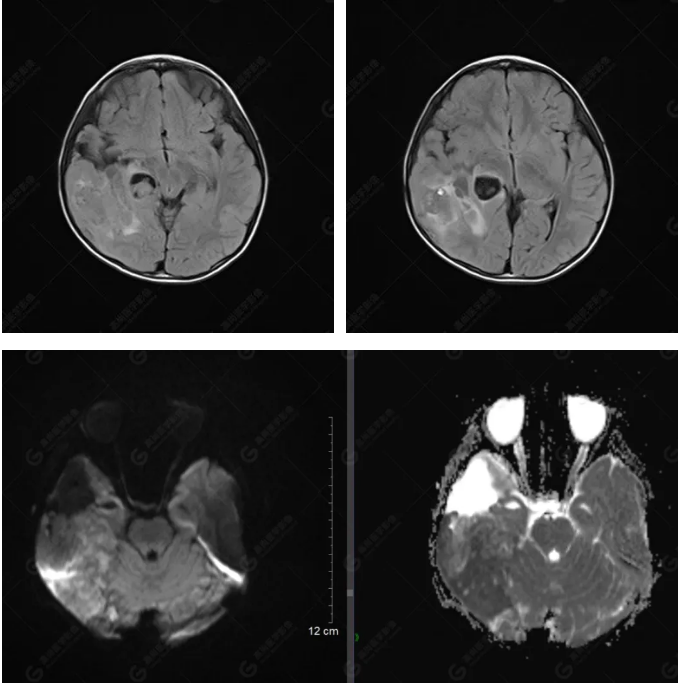

右側(cè)顳葉腫瘤切除術(shù)后(具體不詳):右側(cè)顳部骨質(zhì)不連續(xù)呈術(shù)后改變,右側(cè)顳葉術(shù)區(qū)見(jiàn)片狀長(zhǎng)T1長(zhǎng)T2信號(hào)影,F(xiàn)LAIR呈低信號(hào);術(shù)區(qū)后方右側(cè)顳枕葉見(jiàn)一巨大占位性病變影,邊界欠清,大小約6.2×5.8×4.3cm(前后×左右×上下),信號(hào)不均勻,T1WI呈等稍低信號(hào)間雜少許高信號(hào),T2WI呈高稍低混雜信號(hào),DWI示部分病灶彌散受限,相應(yīng)ADC圖減低,磁敏感序列見(jiàn)部分呈極低信號(hào),增強(qiáng)掃描可見(jiàn)明顯不均勻強(qiáng)化,鄰近硬腦膜及小腦幕增厚并明顯強(qiáng)化;另延髓右前方及右側(cè)橋小腦角區(qū)見(jiàn)一不規(guī)則形異常信號(hào)影,大小約3.2×1.3×3.7cm(左右×前后×上下),呈長(zhǎng)T1稍長(zhǎng)T2信號(hào),F(xiàn)LAIR呈等信號(hào),DWI未見(jiàn)受限,增強(qiáng)后明顯均勻強(qiáng)化,鄰近腦膜明顯強(qiáng)化。鄰近腦實(shí)質(zhì)及右側(cè)顳角明顯受壓;左側(cè)大腦半球未見(jiàn)局灶性信號(hào)異常,中線結(jié)構(gòu)稍左移。

右側(cè)顳葉腫瘤切除術(shù)后:現(xiàn)術(shù)區(qū)后方右側(cè)顳枕葉及延髓右前方占位,右側(cè)顳枕部硬腦膜及小腦幕明顯強(qiáng)化,結(jié)合既往影像資料,考慮為胚胎源性惡性腫瘤,如非典型畸胎樣/橫紋肌樣瘤(AT/RT)或原始神經(jīng)外胚層腫瘤(PNET)。

非典型畸胎樣/橫紋肌樣瘤(AT/RT) 是一種高度惡性中樞神經(jīng)系統(tǒng)腫瘤,臨床罕見(jiàn),臨床表現(xiàn)無(wú)特異性,好發(fā)于 5 歲以下兒童,尤以 3 歲以下多見(jiàn),在兒童原發(fā)性中樞神經(jīng)系統(tǒng)(CNS)腫瘤中占 1%~3%。該腫瘤體積一般較大,幕上大于幕下,有明顯的占位效應(yīng)。該腫瘤成分復(fù)雜,囊變、出血、壞死常見(jiàn)。因此 AT/RT信號(hào)混雜,囊性部分呈 T1WI低、T2WI高信號(hào),增強(qiáng)后不強(qiáng)化;若瘤體出血,囊內(nèi)可見(jiàn)T1WI稍高信號(hào)、T2WI低信號(hào),實(shí)性部分在 T1WI上呈混雜等、低信號(hào),在T2WI 及 T2-FLAIR上呈混雜等高信號(hào),增強(qiáng)掃描后大部分呈環(huán)形條帶樣明顯強(qiáng)化,中心壞死區(qū)不強(qiáng)化。另外,該腫瘤實(shí)性成分在DWI上呈高信號(hào),說(shuō)明腫瘤細(xì)胞核密集,水分子擴(kuò)散明顯受限,提示該腫瘤惡性程度高,容易復(fù)發(fā)及轉(zhuǎn)移。